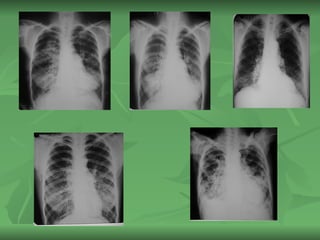

BRONQUIECTASIA Diagnóstico :  Los estudios deben dirigirse en primer lugar a confirmar el diagnóstico de sospecha. El diagnóstico positivo se hará ante todo paciente que se queje de tos crónica, productiva, con o sin hemoptisis y que halla tenido episodios recidivantes de neumonía con radiografías de Tórax

BRONQUIECTASIA Exámenes Complementarios : Rx de Tórax:  Puede ser normal, sobre todo en las fases iniciales de la enfermedad, otras veces lo único que se aprecia son lesiones lineales inespecíficas en la base pulmonar u otro sitio. Broncoscopía:  Solo se realizará cuando es necesario tomar una decisión terapéutica de tipo quirúrgica

BRONQUIECTASIA Exámenes Complementarios: Rx de Tórax: Puede ser normal, sobre todo en las fases iniciales de la enfermedad, otras veces lo único que se aprecia son lesiones lineales inespecíficas en la base pulmonar u otro sitio. Broncoscopía: Solo se realizará cuando es necesario tomar una decisión terapéutica de tipo quirúrgica